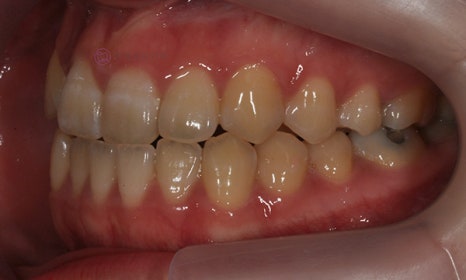

위 환자분은 치아 중심선이 맞지 않는다는 주소로 치과에 내원하셨습니다. 미소시 사진을 보면 위 치아도 오른쪽(사진 상 왼쪽)으로 틀어져 있고, 아래 치아도 왼쪽(사진 상 오른쪽)으로 틀어져 있었습니다. 그리고 양쪽 입꼬리 근육의 활성도도 차이가 있어서, 웃었을 때 왼쪽 입꼬리가 오른쪽보다 덜 올라가서 비대칭이 더 강조되어 보였습니다.

2020.7

치아 중심선의 차이를 개선하고, 얼굴의 중심과 치열의 중심을 맞춰주기 위하여 오른쪽 아래 작은 어금니를 하나만 발치하여 그 공간으로 아래 치열을 오른쪽으로 돌려주고, 위 치열은 전체적으로 왼쪽으로 치열을 이동시켜서 중심선을 맞추어 주었습니다.